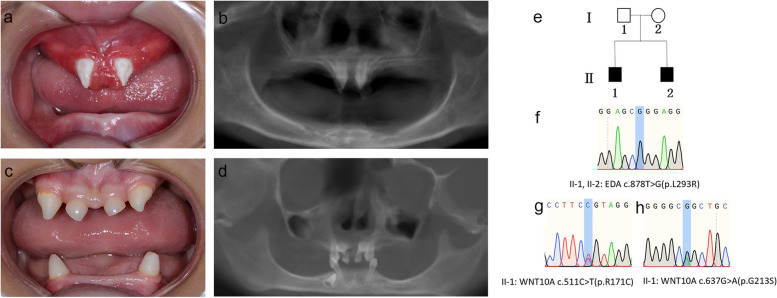

兩名分別為11歲和8歲的親兄弟因先天性牙齒缺失被轉(zhuǎn)診至同佳學(xué)基因具有合作關(guān)系的武漢大學(xué)口腔中心就診。經(jīng)患兒母親及兩名患兒本人簽署知情同意書后,醫(yī)護人員收集了兩位患兒的病史資料,拍攝了相關(guān)臨床照片,并采集了外周靜脈血樣本外送到佳學(xué)基因檢測進(jìn)行致病基因鑒定基因解碼分析。這對兄弟被診斷為低汗性外胚層發(fā)育不良(HED),均表現(xiàn)出典型的臨床特征,包括少牙(hypodontia)、毛發(fā)稀疏(hypotrichosis)、少汗(hypohidrosis)以及面部發(fā)育異常(facial dysmorphism)。有趣的是,哥哥的牙齒發(fā)育不全明顯比弟弟更為嚴(yán)重。哥哥下頜完全無牙,僅保留上頜兩顆中切牙;而弟弟則仍有部分前牙萌出。

體格檢查顯示,這對兄弟均表現(xiàn)出頭發(fā)稀疏、牙齒缺失及汗腺發(fā)育不良(圖1a-d)。兩人均具有X連鎖低汗性外胚層發(fā)育不良(HED)的典型面容特征:鞍鼻、嘴唇厚大、下頜尖翹以及眼周黑眼圈。

口腔檢查及錐形束CT(CBCT)掃描結(jié)果提示,哥哥(II-1)的所有乳牙及大多數(shù)恒牙均先天缺失,僅保留兩顆錐形上中切牙(#11、21)(圖1a-b)。由于下頜牙列完全缺失,他無法正常咀嚼或建立咬合關(guān)系。

弟弟(II-2)尚保留6顆乳牙(#51、53、61、63、73、83)及3顆恒牙胚(#11、21、43)(圖1c-d)。

Fig. 1

圖1:HED兄弟患者的牙齒特征與面部表現(xiàn)

a-b:**兄長(II-1)**的口腔狀況及全景X線片。

c-d:弟弟(II-2)的口腔狀況及全景X線片。

e:家系圖,黑色方塊代表HED患者。

f:DNA測序圖譜顯示兩位兄弟(II-1,II-2)攜帶

EDA基因雜合變異c.878T>G(p.L293R)

g-h:兄長(II-1)同時攜帶兩個WNT10A基因雜合變異:c.511C>T(p.R171C)和 c.637G>A(p.G213S)。

在兩兄弟中均檢測到EDA基因c.878T>G(p.L293R)的錯義變異,但復(fù)合雜合型WNT10A基因變異(c.511C>T(p.R171C)和c.637G>A(p.G213S))僅在兄長中發(fā)現(xiàn)。

母親臨床表型正常,未出現(xiàn)毛發(fā)、汗腺或牙齒相關(guān)異常。WES檢測顯示其為EDA基因c.878T>G雜合變異及WNT10A基因c.511C>T雜合變異的攜帶者。上述結(jié)果均經(jīng)Sanger測序驗證(圖1e-h)。